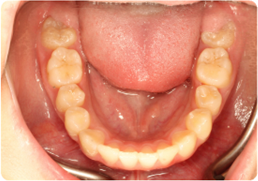

Each case shows the front view and an arch or side view, before and after BioLign Method-guided treatment.

All cases treated within 6–12 months.

Misaligned lower arch corrected with coordinated expansion